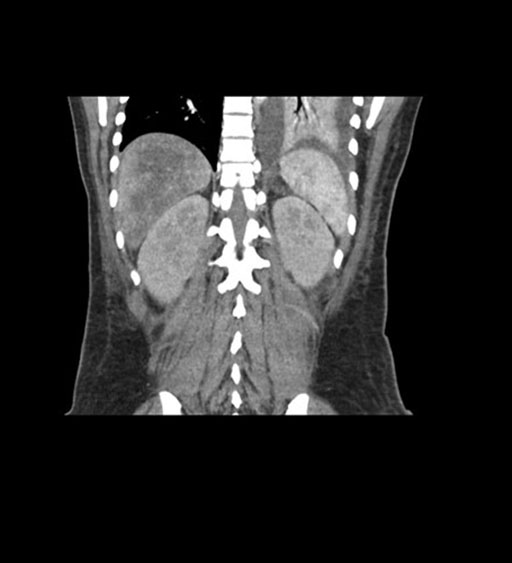

Coronal Arterial

Imaging analysis

Based on initial findings, which issue(s) would you be most concerned about?